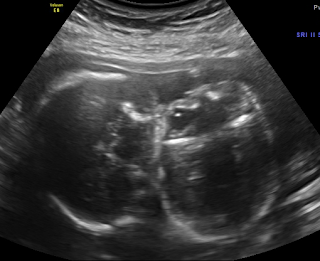

Here are some pictures we wanted to share with everyone :)

This is the both babies legs and feet all together. I love this picture!

Profile view of one baby with her hand up by her face

Another profile view of her with hand by her mouth

Arm and hand

The babies legs. Their knees are touching in this one

Another shot of one of the babies legs

Baby B...cute little face! We had a hard time getting one of her face because she is facing down towards my spine

Another one of an arm and hand

Looking down at both of the babies heads

Leg and foot

Baby A...another cute little face!